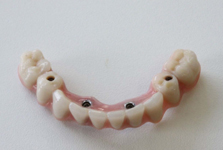

Protetické řešení může být pomocí můstku, který je kotvený na implantátech nebo pomocí jednotlivých korunek na implantátech.

V zásadě je možné do těchto můstků zařadit i přirozené zuby, zejména pokud je potřeba tyto zuby ošetřit proteticky

- korunkami. Korunky nebo můstky mohou být na implantáty nacementovány nebo přišroubovány.

Zdravé zuby zůstanou zachovány a přitom náhrady jsou pevné, jako na vlastních zubech